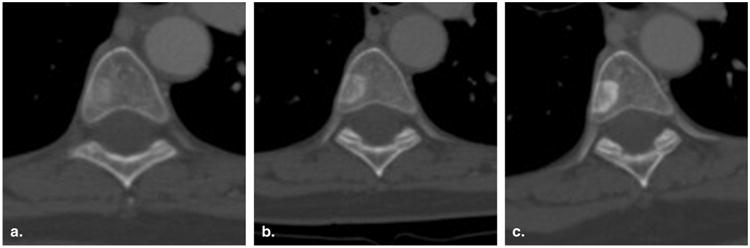

Figure 5.

Incorrect assignment of progressive disease for a nontarget lesion (60-year-old female with breast cancer). Contrast-enhanced computed tomography of the chest viewed at bone window settings demonstrates a vertebral body metastasis becoming more sclerotic at baseline (a), 8 weeks (time point #1) (b), and 16 weeks (time point #2) (c). Because this could represent a treatment response rather than worsening disease, it would be inappropriate to assign progressive disease to this lesion.